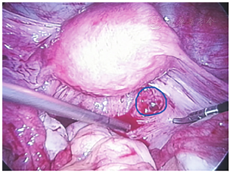

患者,32岁,因"停经33 d,阴道少量出血4 d伴下腹痛1 d"于2018.04.20入院。该患者既往月经规则,周期为30 d,经期7 d,末次月经2018.03.18;2018.04.17起出现点滴状阴道流血,2018.04.19出现下腹痛,为持续性,渐加剧,伴有肛门坠胀感。既往生育史:1-0-0-1,2010年剖宫产,产后6个月置宫内节育器避孕。妇科检查:外阴已婚式;阴道见少量暗红色血液,后穹窿触痛明显,未及结节和包块;宫颈光,有举痛;宫体前位,饱满,无压痛;右侧附件深压痛,未及包块,左侧附件无压痛,未及包块。血人绒毛膜促性腺激素(hCG)2 095.00 IU/L,孕酮33.35 nmol/L。阴道B超提示:子宫后方略偏右侧混合性回声占位35 mm×33 mm×54 mm,盆腔积液约40 mm。入院后患者腹痛较剧烈,急诊给予腹腔镜下探查术,术中吸出盆腔游离血和血块约400 mL。子宫前位,饱满,双侧输卵管外观形态正常,未见增粗,未见渗血,左侧卵巢3 cm×3 cm×2 cm大小,右侧卵巢3 cm×2 cm×1 cm大小,未见破口,在盆腔血块中未见绒毛,于是探查上腹部肝脾未见出血灶,术中观察到子宫直肠陷凹鲜红色血液缓慢增多,吸净后仔细观察,右侧宫骶韧带内侧的后腹膜处有一针尖样出血点,血液从此处不断缓慢流出,反复挤压,总有血块和血液被挤出,最后挤出一1 cm×0.5 cm×1 cm大小的绒毛(图1),给予间断缝合2针,创面无明显出血。术后病理:血块中见绒毛。术后11 d血hCG下降至正常,恢复好。

近年来异位妊娠的发病率逐渐增高,随着诊断技术的提高,处理也愈加及时有效。尤其是腹腔镜微创技术的发展,使异位妊娠基本达到"即诊即治"。病例1,因急性腹腔内出血行腹腔镜下探查术,常见异位妊娠部位输卵管、卵巢、子宫浆肌层、阔韧带等未见出血部位和包块的情况下,扩大探查范围,最终在骶骨韧带内侧的后腹膜发现了针尖样出血点,初以为患者有外院就诊经过,是否为后穹窿穿刺所致,经过反复局部出血点周围探查,最终挤压出血块并带有绒毛组织。从该病例我们得到经验,有的异位妊娠的部位特别,我们一定要仔细探查盆腹腔的每一部位,多思考,争取观察到出血点和绒毛,必要时请相关科室协助探查。复习文献,目前国内外病例报道腹膜后妊娠仅20余例[6,7,8,9],比较罕见。因一般情况下,腹腔为相对封闭环境,腹膜光滑,无缝隙,受精卵在腹膜后着床可能性不大。分析腹膜后妊娠的发病原因可能是:①长期炎症反应或子宫内膜异位症导致局部腹膜相对薄弱并形成缺损,受精卵通过缺损着床于腹膜后,而腹膜后血运丰富,受精卵得到营养而分化发育;②妊娠滋养细胞是一种在组织发生学、细胞属性、形态特征上均有别于体细胞的具有独立生物学行为的特殊细胞,其生物学行为更接近于恶性肿瘤细胞,具有侵袭母体组织和血管的特点[10]。受精卵着床于后腹膜,并引起后腹膜的缺损,通过缺损,着床于腹膜后。总之,早期腹膜后妊娠症状不典型,容易被误诊为一般的异位妊娠,术前诊断的病例几乎没有,确诊必须根据手术探查及病理所见。术后需随访血hCG,以排除滋养细胞肿瘤和持续性异位妊娠。